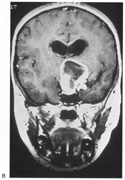

The upper and lower banks can also be involved separately. Ischemia can do this because the banks have separate blood supplies. Upper bank infarcts cause homonymous contralateral inferior quadrantanopia (Fig. 10) and lower bank infarcts cause superior quadrantanopia. Although altitudinal defects have been reported occasionally,47,48 most quadrantic defects do not align at the horizontal meridian, because the upper field merges without interruption into the lower field in the depths of the calcarine fissure. Thus it has been argued that quadrantic defects that respect the horizontal meridian are caused by involvement of area V2, surrounding striate cortex,49 which remains controversial. Quadrantanopias are three times more common with striate lesions than with optic radiation lesions.33 Striate quadrantanopias are more frequently isolated signs but can be associated with other signs of higher cortical visual dysfunction, such as pure alexia or hemiachromatopsia, whereas optic radiation quadrantanopias usually are accompanied by hemiparesis, dysphasia, or amnestic problems.33

Fig. 10. Striate quadrantanopia. A. A 68-year-old woman with a stroke 3 years previously, causing left inferior quadrantanopia. B. MRI shows infarct of the superior bank of the right calcarine cortex.